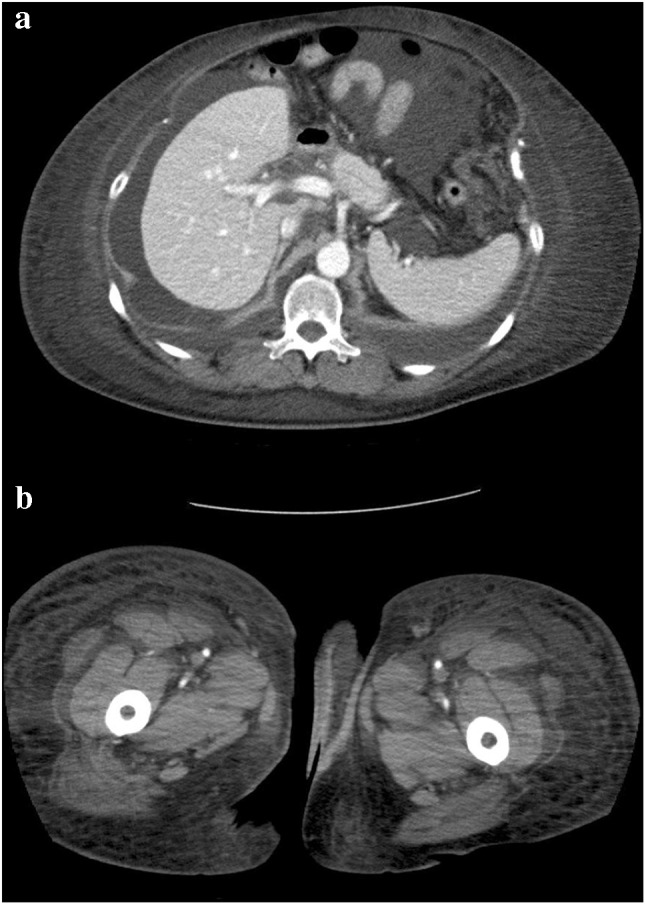

Fig. 1.

A chest computed tomography scan shows bilateral pleural effusion and pericardial effusion before pericardial drainage and thoracocentesis

4 months after initial pericardiocentesis, the patient was admitted for the aggravation of dyspnea because of the recurrent retention of pericardial effusion, and active anticancer treatment was discontinued. Pericardiocentesis was repeated, and 200 mL of pale bloody pericardial effusion was drained. Pericardial effusion became subcutaneously retained in the trunk below the puncture site over the lower limbs via the drainage route. Edema in the trunk below the abdomen and lower limbs gradually aggravated over time (Figs. 2, 3). A puncture was performed after 3 months to treat recurrent retention of pleural effusion. In contrast, the patient’s pericardial effusion did not recur. Flexion of the knee joint gradually became difficult because of marked edema in the trunk over the lower limbs. The skin extended and became sclerotic because of severe edema, liquid leaked from abdominal skin injuries, and the condition became similar to skin lymphorrhea in lymphedema. The skin injury regions were managed using an ostomy pouch. Retention of pleural effusion recurred; however, puncture was not performed because the patient’s general condition was poor and her prognosis was judged to be limited. Her symptoms were relieved by morphine. Home care was continued, and the patient died 9 months after the diagnosis of recurrence. During that period, the retention of pericardial effusion did not recur. Her next of kin provided informed consent for the publication of this case report.

Fig. 2.

a An abdominal computed tomography scan shows pleural effusion, ascites, and subcutaneous edema in the lower trunk after re-pericardiocentesis. b A computed tomography scan shows subcutaneously edema in the bilateral femurs after re-pericardiocentesis